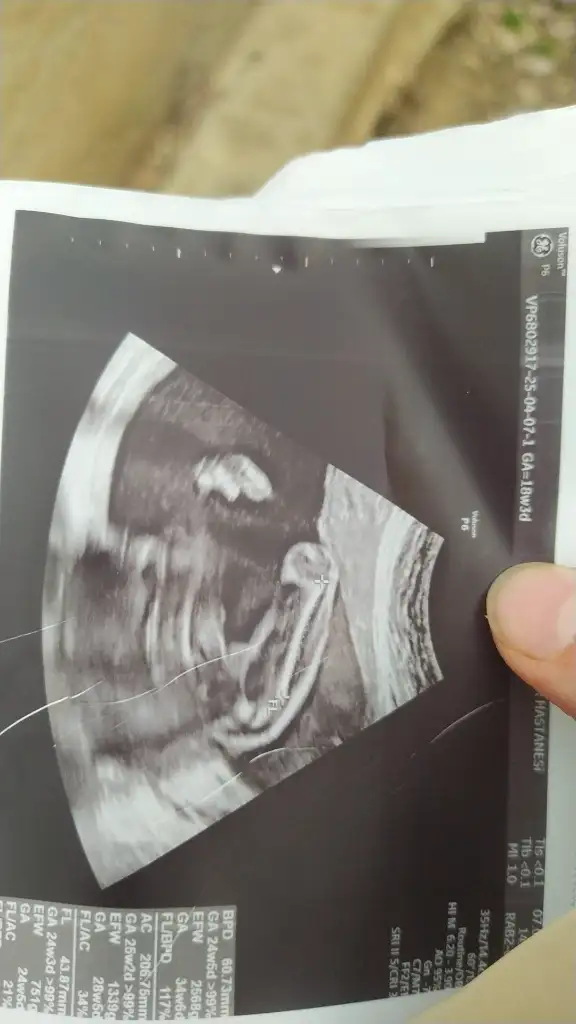

Bunlarada bakabilir misiniz

bacak arası görüntü anlamıyorum canımBunlarada bakabilir misiniz

6 haftalık vajinal ultrason görüntüsü bize de bakabilir misiniz lütfen teyzeleri, teşekkür ediyorum şimdidenKızlar bebişlerinizin ultrason resimlerini ve cinsiyetini kaçıncı haftada olduklarını yazında kendi ultrason resimlerimizle kıyaslayıp fikirde bulunalım. Nub teorisi, kafa şekli, kemik yapısından cinsiyet teorileri tutuyor mu bakalım bir